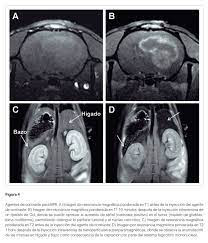

En la resonancia magnética, se detectan las propiedades magnéticas de las moléculas. Durante la hiperpolarización, estas propiedades se amplifican significativamente durante un cierto período, lo que da como resultado una señal mucho más fuerte de lo habitual. Biológicamente, las moléculas se comportan como antes. Por lo tanto, los procesos metabólicos se pueden observar de forma no invasiva. Este método es seguro, no requiere radiación y la RM metabólica solo toma unos minutos.

1. Producción exitosa de piruvato altamente polarizado en una solución acuosa biocompatible. El piruvato es una molécula común en el cuerpo y está involucrada en los procesos metabólicos centrales. El equipo utilizó el innovador método SABRE (amplificación de señal por intercambio reversible) para mejorar la señal de piruvato. Este proceso permite la producción de agentes de contraste biológicos altamente sensibles en pocos minutos, a bajo costo y sin modificación química. Hasta ahora, SABRE no ha sido lo suficientemente eficaz como método y anteriormente no era posible producir agentes de contraste en soluciones acuosas con suficiente pureza. Por el contrario, con el método actualmente establecido, la producción de agentes de contraste tomó aproximadamente una hora o más y fue técnicamente muy exigente.

2. Con los agentes de contraste biológicos altamente sensibles desarrollados, la conversión de piruvato en lactato y alanina se demostró con éxito en un modelo animal. Estas conversiones en el metabolismo energético ya se han identificado como marcadores diagnósticos útiles en estudios previos.